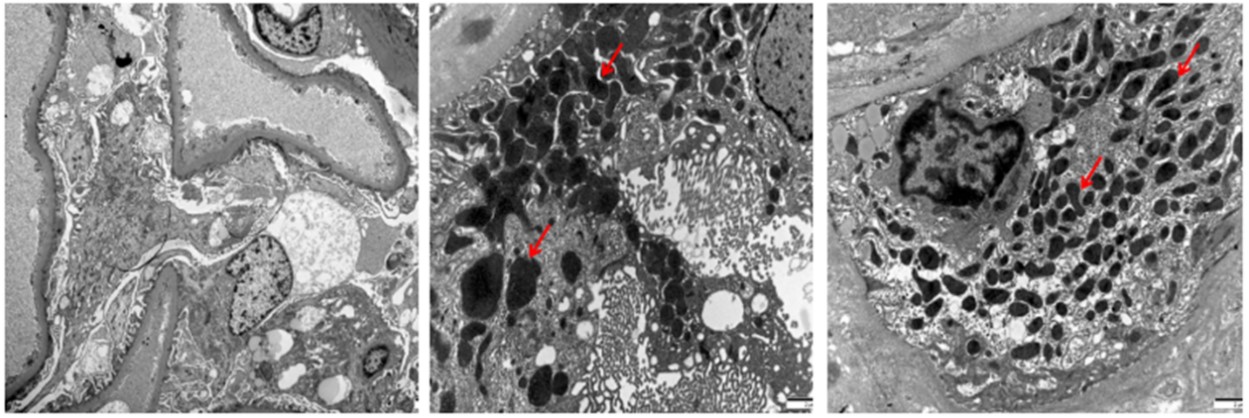

肾脏病理显示:光镜28个肾小球,其中15个呈缺血性硬化伴肾小管多灶性萎缩,2个肾小球呈节段性硬化伴玻璃滴样病变。其余肾小球可见系膜基质轻度增多所致的系膜区轻度增宽(图1)。此外,可见局灶性肾小管萎缩和间质纤维化。间质炎性浸润通常极少。免疫荧光显示肾小球基底膜或系膜区有IgG沉积,而无IgA、IgM、C3、C1q、Kappa和Lambda沉积(图2)。电镜:肾小球基底膜增厚波动于290-350nm,系膜细胞及基质轻度增生,足突融合40%,可见肾小管上皮细胞胞质内大量变性肿胀及异型性线粒体(图3),肾间质淋巴单核细胞浸润伴胶原纤维形成。 病理诊断:1.局灶节段肾小球硬化症,继发于线粒体性糖尿病。2.糖尿病小血管病变。3.肾脏损伤类型及特征:肾小球轻度增生,缺血性硬化肾小球(12/28),局灶节段门部型硬化肾小球(1/28),局灶节段非特殊型硬化肾小球(1/28),中度肾小管萎缩/间质纤维化(30%),小动脉管壁明显增厚,出入球小动脉均质玻璃样变。4.肾活检组织慢性病变程度评分:GS:2,IF:2,TA:2,CV:1,中度慢性。

图3.肾组织电镜分析(×4000)。可见足突节段性融合及形态异常的线粒体。可见系膜基质轻度增多,但肾小球基底膜未见明显改变。